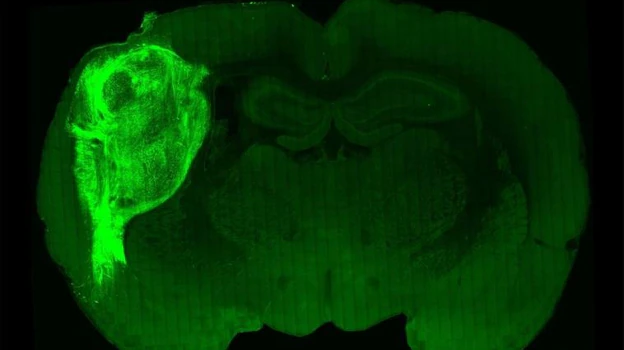

Uno de los últimos estudios más rompedores, publicado en la misma revista a finales del pasado año, daba un paso más allá: el grupo liderado por Sergiu Pasça, investigador en la Universidad de Stanford y una de las figuras más relevantes del trabajo con organoides, conseguía insertar estos minicerebros a partir de células humanas en cerebros de rata y que, además, este injerto reaccionara cuando los animales recibían una recompensa.

«Fue un hito porque estos organoides no crean tejidos conectivos, como venas y arterias, por lo que trasplantarlos a organismos vivos es muy complicado», explica a ABC Guillermina López-Bendito, también investigadora del Instituto de Neurociencias CSIC-UMH y colaboradora del laboratorio de Pasça. La clave estuvo en incluir estos organoides en el sitio y momento exactos: en la corteza somatosensorial –el área responsable de recibir y procesar información sensorial de todo el cuerpo, como el tacto– de ratas jóvenes, cuyos circuitos neuronales aún no están completamente formados.